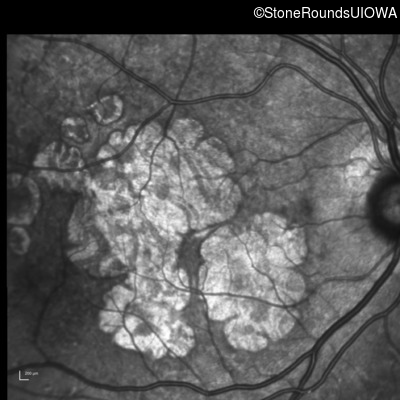

Infrared Fundus Photograph - Right - 20/25

Exemplar

Infrared Fundus Photograph - Left - 20/25 -2